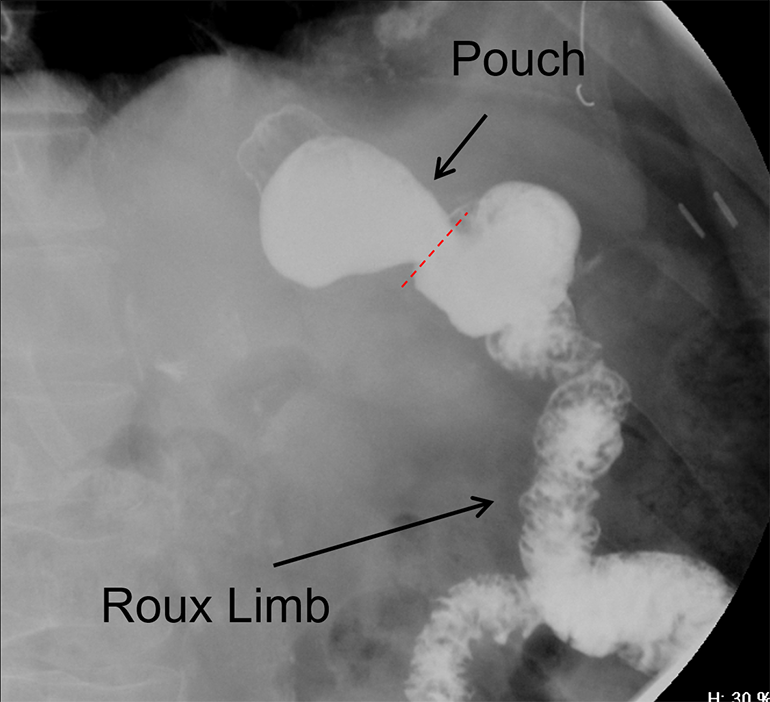

- The technologist will obtain a scout radiograph to include the upper abdomen. Evaluate for the location of the surgical chain sutures

(key image 1).

- There are usually two "sets" of surgical chain sutures.

- The first is located in the epigastric area at the level of the gastrojejunal anastomosis.

- The second is usually located in the left midabdomen. This is the site of the jejunojejunal anastomosis.

- Position the patient in the right posterior oblique position and have the patient take a sip of contrast material.

- Obtain a spot film of the contrast material filling the gastric pouch and proximal roux limb

(key image 2).

- Repeat steps b and c except have the patient positioned in the left posterior oblique position

(key image 3).